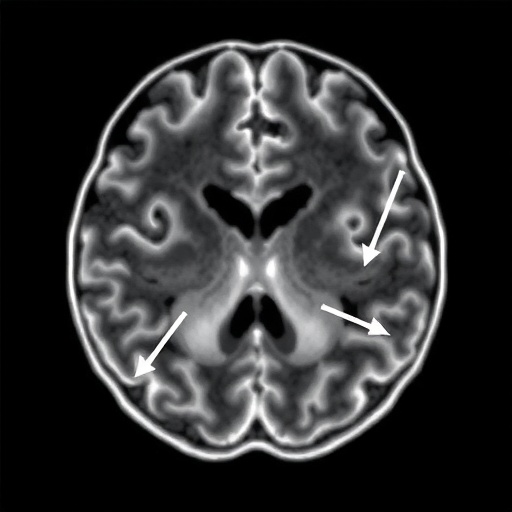

Diving deeper into the technicalities of the study, the researchers observed that it isn’t just the absolute speed of blood but the asymmetry of velocities across the brain’s hemispheres that provides the most definitive clues. In many cases of Moyamoya, the disease progresses unevenly, creating a hemodynamic imbalance that further stresses the fragile “puff of smoke” vessels. The study’s data indicates that when one side of the brain shows a dramatic spike in velocity compared to the other, the risk of a localized stroke or “silent” infarct increases exponentially. This nuanced understanding of intracranial hemodynamics allows for a more personalized approach to medicine, where treatment plans are tailored to the specific flow patterns of an individual’s brain rather than a one-size-fits-all protocol based on general age or symptom presentation.